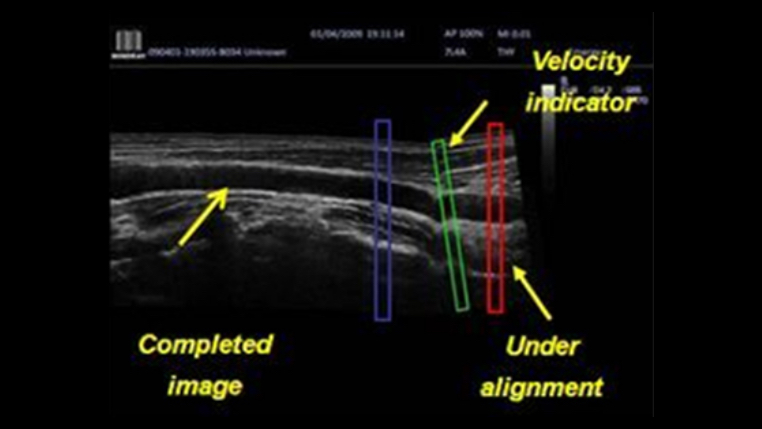

iScape™ (Real-time Panoramic Imaging)

Get a complete and extended view of the anatomical structure through panoramic imaging, coupled with velocity indication and forward/backward scan ability making scanning much easier, smoother and more controllable.